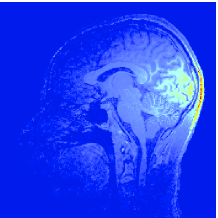

Another application example of primal-dual proximal algorithms is Parallel Magnetic Resonance Imaging (PMRI) reconstruction. A set of measurement vectors is acquired from coils. These observations are related to the original full FOV (Field Of View) image corresponding to a spin density. An estimate of is obtained by solving the following problem:

where , is the noise covariance matrix for the -the channel, is a diagonal matrix modelling the sensitivity of the coil, is a 2D discrete Fourier transform, is a subsampling matrix, is a sparsity measure (e.g. a weighted -norm), is a (possibly redundant) frame analysis operator, and is the indicator function of a vector subspace of serving to set to zero the image areas corresponding to the background.777 denotes the transconjugate operation and designates the lower rounding operation. Combining suitable subsampling strategies in the k-space with the use of an array of coils allows us to reduce the acquisition time while maintaining a good image quality. The subsampling factor thus corresponds to an acceleration factor. For a more detailed account on the considered approach, the reader is refered to [99, 100] and the references therein. Reconstruction results are shown in Fig. 8. Fig. 9 also allows us to evaluate the convergence time for various algorithms. It can be observed that smaller differences between the implemented primal-dual strategies are apparent in this example. Due to the form of the subsampling matrix, the matrix inversion involved at each iteration of ADMM however requires to make use of a few subiterations of a linear conjugate gradient method.